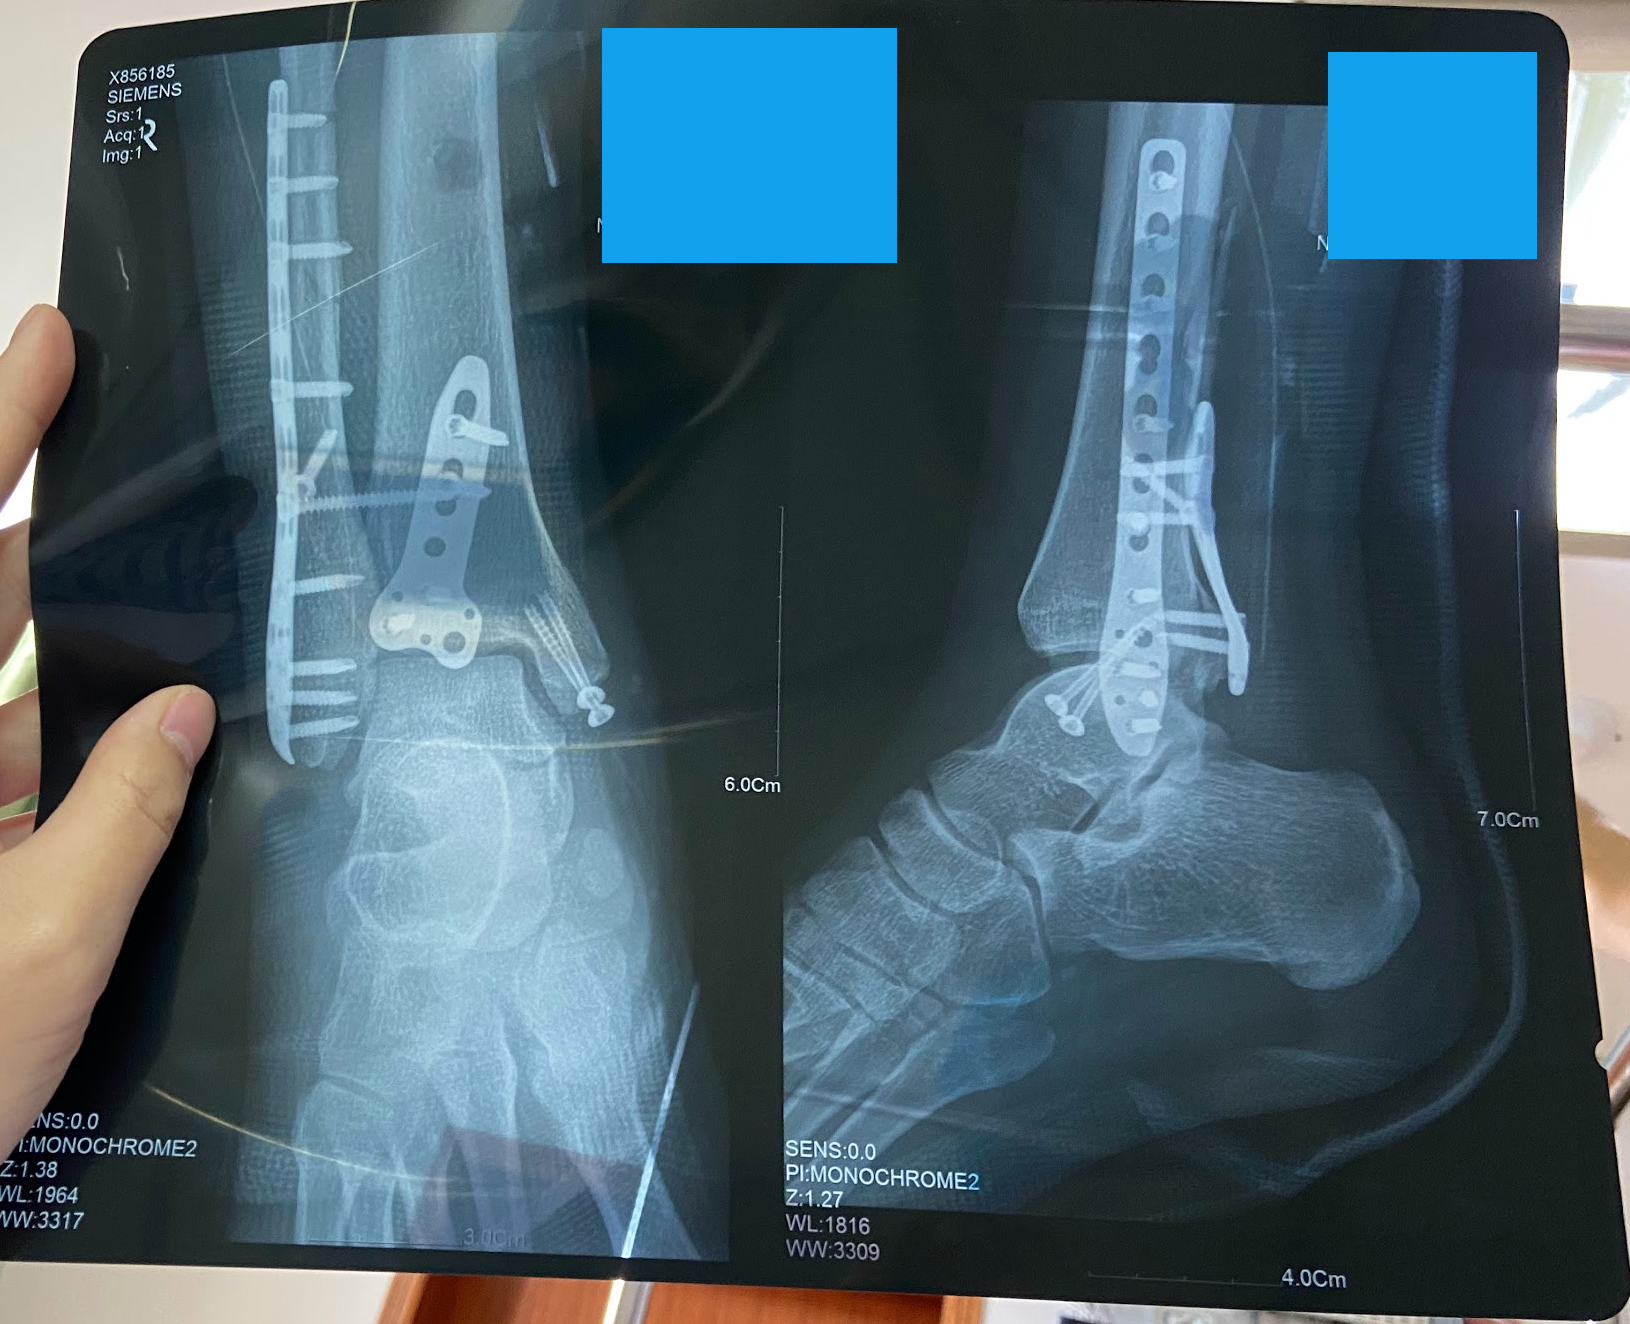

2021 年 12 月 31 日跨年夜当晚发生了一个不大不小的意外: 在各种机缘巧合下我的右脚踝发生了三踝骨折 (见下图).

最终整个过程前前后后花费了五个月, 结果就是🎓毕业设计被我马马虎虎地糊弄过去, 其中有三个月的时间都在床上度过.